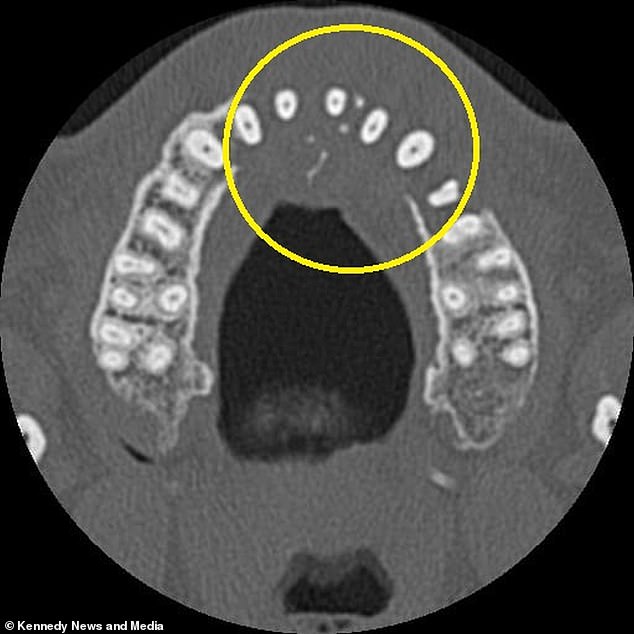

Further tests, including a CT scan, uncovered a tumor growing in his sinus cavity, extending toward his nose. The diagnosis came as a shock: stage two diffuse large B-cell lymphoma (DLBCL), a type of non-Hodgkin lymphoma that affects white blood cells. X-rays confirmed the tumor had eroded his jawbone, and the disease had already begun spreading to his neck.